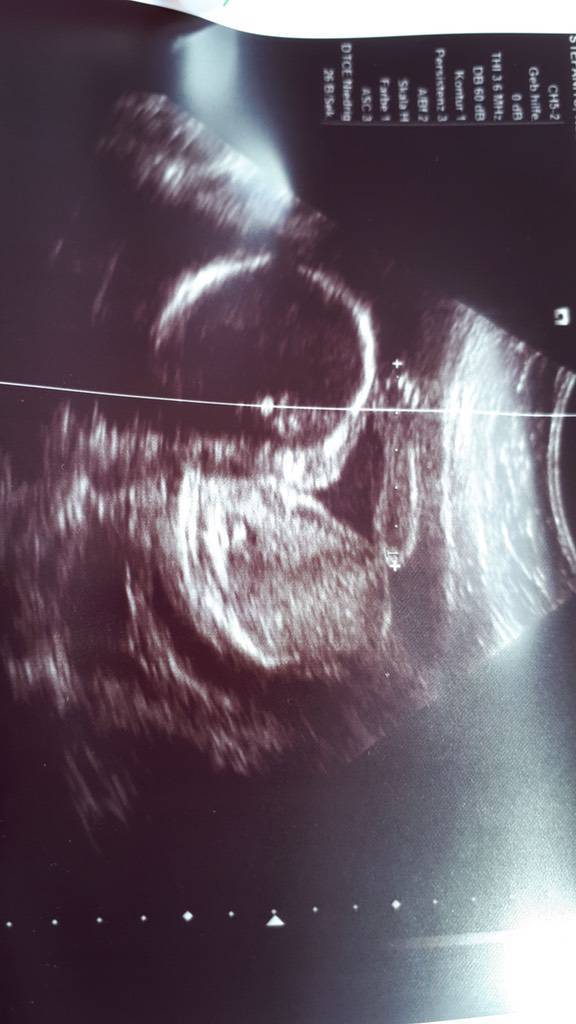

war gerade beim US, Babys wiegen 2554g und 2698g und sind somit 4 Tage bzw. 8 Tage weiter